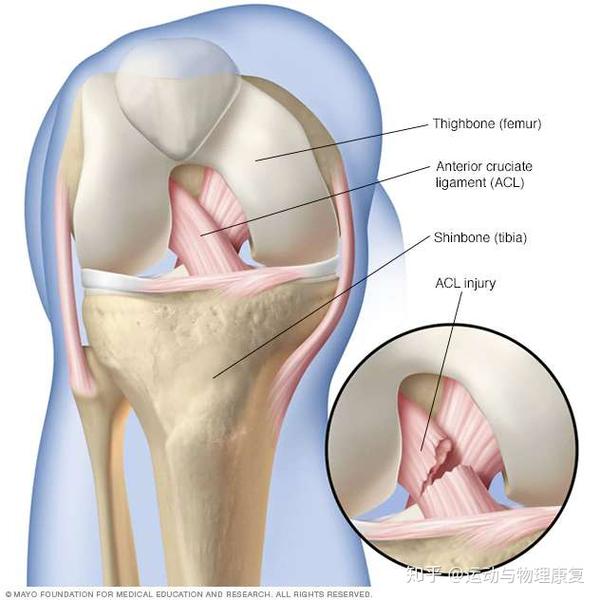

膝前十字靱帯 (ACL)損傷とは 膝には、関節の動きをコントロールする4本の靱帯があります。 前十字靭帯はそのうちの一つで、膝が伸びすぎないように抑えたり、膝の前ずれや捻りの方向への動きを制御をしています。 ジャンプの着地や急な方向転換、相手Acl術後の固有感覚の回復過程について,術後6か月で 正常な機能に戻るという報告がある4).今回の総軌跡長の 変化では,男女とも経時的に有意な減少を認め,術後6か 月以降に安定する傾向を示し,同様の結果が得られたと考 acl再建術後患者のスポーツ復帰において、テーピング、装具または両方の併用、いずれが推奨されるか? 確認 7 acl再建術後のスポーツ復帰基準において筋力、関節可動域、動作いずれが判断材料として推奨されるか? 確認 8

Acl再建術後の留意点 1 再断裂やゆるみの可能性について 2 術後の靭帯は、手術直後から3~4ヶ月程度はかなり弱いため、無理な運動や過度の力がかか れば伸びたり、切れてしまう可能性があります。Acl術後では、方向転換・ジャンプ・着地・カッティング・減速動作など、acl損傷の受傷機転になりうる動作の獲得が最も難しいと言われています。 これらは 損傷した膝の不安定性や筋力の回復の程度が動作に影響します 。• ACL 損傷は、頻度の高い膝関節外傷であり、 損傷によりスポーツ活動が著しく制限される • ACL再建術後の合併症のうち、伸展制限は 重要なものの1つである Gobbi et al Clin Orth 12 Hamidreza Y J Ortho Traum16